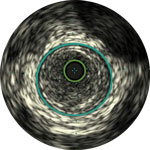

Die IVUS-Technologie von Philips liefert detaillierte Läsionsbilder, die Ihnen die Entscheidung über das optimale Vorgehen erleichtern.

Eine Angiographie liefert Informationen über die luminalen Eigenschaften peripherer Arterien, unterbewertet aber das Ausmaß der Atherosklerose bei Patienten mit peripherer arterieller Verschlusskrankheit (pAVK) erheblich, selbst bei „normal erscheinenden“ Gefäßen.1

Dr. Stavroulakis erörtert, wie der Schweregrad einer pAVK durch eine reine Angiographie häufig unterschätzt wird und wie mithilfe von IVUS der prozentuale Stenosegrad und die Plaque-Belastung präzise gemessen und quantifiziert werden können.